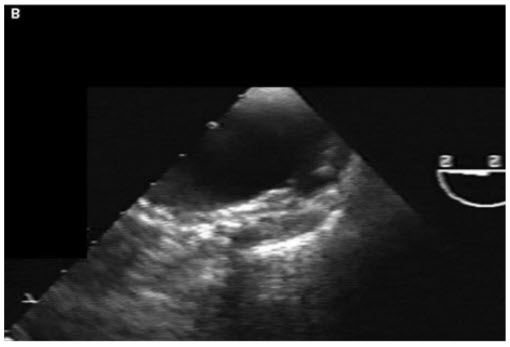

Despite severe atheroma in the aorta, the physician taking care of the patient is not convinced that he does not have an acute coronary syndrome and performs a cardiac catheterization. It shows that the grafts are patent and there is no culprit lesion in the native vessels. He then decides to perform aortography and a focal outpouching is seen in the aortic wall in the distal ascending aorta (Fig. below).

Contrast dye collects slowly in this region. The patient’s chest pain is intensifying. A TEE is also performed (Fig. below).

What is the correct diagnosis?

What is the most appropriate next management step to take?